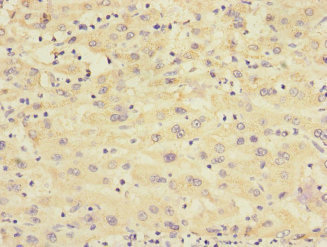

Immunohistochemistry of paraffin-embedded human liver cancer using CSB-PA873646DSR1HU at dilution of 1:100